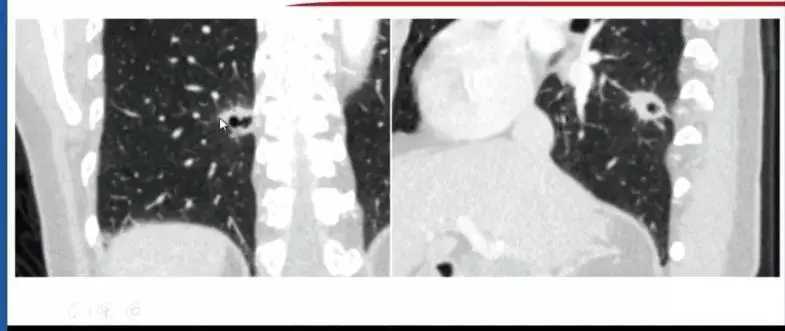

3. 肺细胞瘤(SP)

曾经被命名为肺硬化性血管瘤(一种较为少见的肺部良性肿瘤)。

通常情况下,肺细胞瘤需与错构瘤进行鉴别诊断,在进行最大密度投影处理后,CT可见肺细胞瘤对周围血管有推移作用。经过影像后处理,可以通过进一步判断肺结节与附近病变和周围血管的关系进行诊断。

图5 图4-5 CT及处理后图像对比,可明确血管推移,进行诊断

图6 三维图像重建图像,此类情况需与肺内肉瘤和小细胞肺癌进行鉴别,嘱患者保持每3个月随访一次

临床工作中肺细胞瘤可能出现周围出血的情况,与错构瘤从影像表现上很难鉴别,伴有肺泡出血的肺细胞瘤会周围会有晕征。